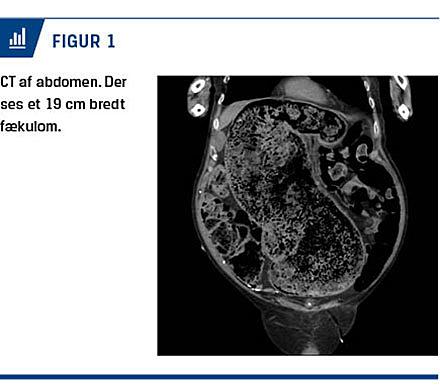

Ved en objektiv undersøgelse fandt man et spændt abdomen, hvorfor der blev foretaget CT af abdomen, hvorved man så en svært dilateret colon med en diameter på op til 19 cm pga. fækalier, men ingen tegn til mekanisk obstruktion eller perforation (Figur 1).